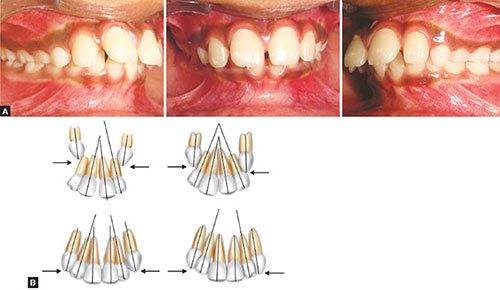

Find ugly duckling stock images in hd and millions of other royalty free stock photos illustrations and vectors in the shutterstock collection. Ugly duckling stage quick reference a stage of dental development usually between the ages of 7 and 12 years preceding the eruption of the permanent canines when the upper central and lateral incisors are tipped laterally due to the crowding created by the unerupted canines to produce a midline space median diastema. Ugly duckling download free clip art with a transparent background on men cliparts 2020.

55 ugly duckling image clipart. Ugly duckling stage is a transient form o. This video was uploaded from an android phone.